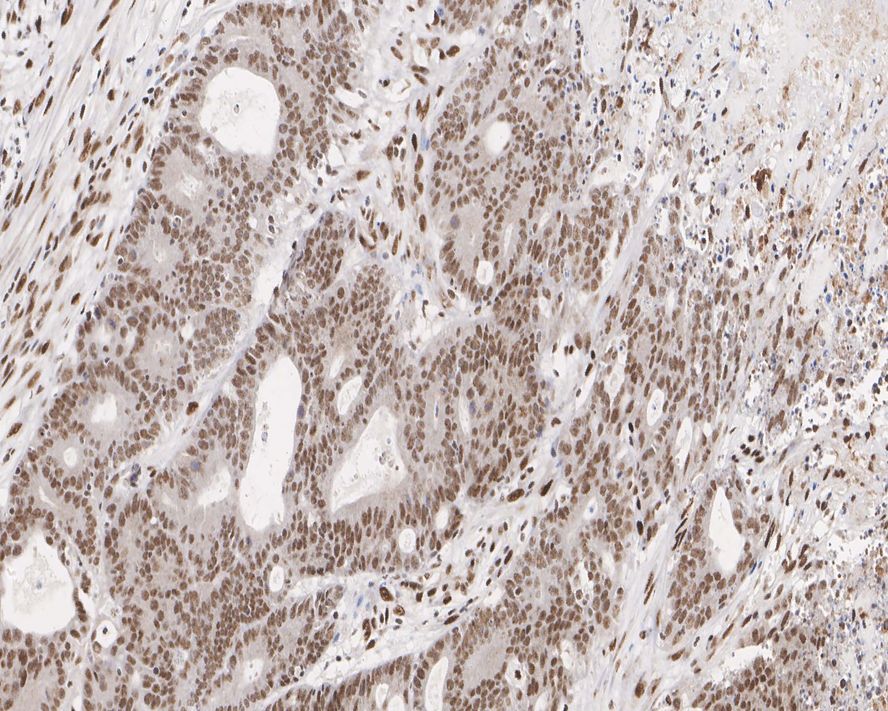

Immunohistochemical analysis of paraffin-embedded human colon cancer tissue with Rabbit anti-MLH1 antibody (HA750749) at 1/400 dilution.

The section was pre-treated using heat mediated antigen retrieval with sodium citrate buffer (pH 6.0) (high pressure) for 2 minutes. The tissues were blocked in 1% BSA for 20 minutes at room temperature, washed with ddH2O and PBS, and then probed with the primary antibody (HA750749) at 1/400 dilution for 1 hour at room temperature. The detection was performed using an HRP conjugated compact polymer system. DAB was used as the chromogen. Tissues were counterstained with hematoxylin and mounted with DPX.